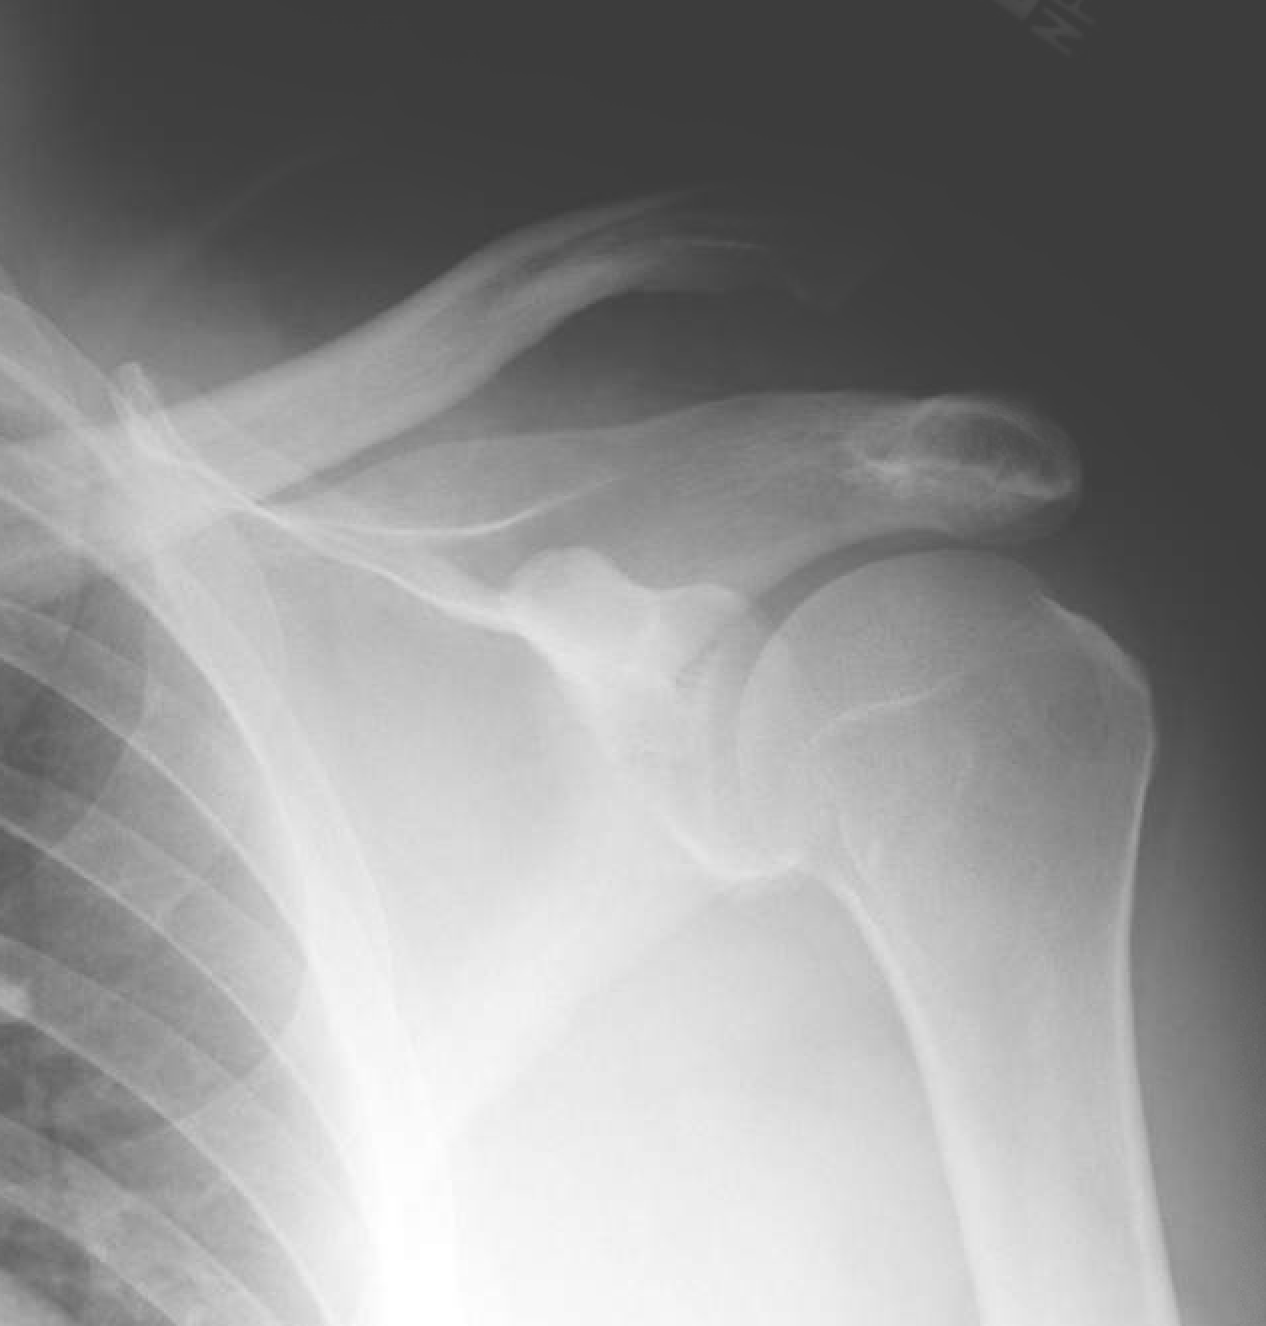

Distal clavicle fractures are traumatic injuries usually caused by direct trauma to the shoulder from a fall in adults. Indicated there was a fracture of the right clavicle, shaft. These deal offers are from many sources, selected by our. Radiographic findings โ€” distal third clavicle fractures are divided into three types based upon fracture site and ligamentous stability (figure 3 โ—among children, 90 percent of clavicle fractures occur in the middle third. Common codes clinical documentation tips clinical scenarios. Symptoms typically include pain at the site of the break and a decreased ability to move the affected arm. It is often caused by a fall onto scapular fracture โ€” infobox disease name = scapular fracture caption = diseasesdb = icd10 cervical fracture โ€” classification and external resources a fracture of the base of the dens ( a part. Subclavian artery or vein injury. Header codes like s42.0 require more digits to indicate the appropriate level of specificity. Regardless of the exact technique used. Clavicle fractures are basically divided into three types based upon location. In children 10 and under, the majority are nondisplaced; Typically, fractured clavicles occur as the result of a direct blow to the shoulder. Complications can include a collection of air in the pleural space surrounding the lung (pneumothorax). Stability of distal fractures can be enhanced by. Bipolar clavicular fractures occur when there are both distal and medial clavicular injuries, most commonly a distal clavicle fracture in combination with an anterior sternoclavicular joint dislocation 8. There is a transverse fracture of the distal left radius just proximal to the wrist joint with dorsal displacement of.